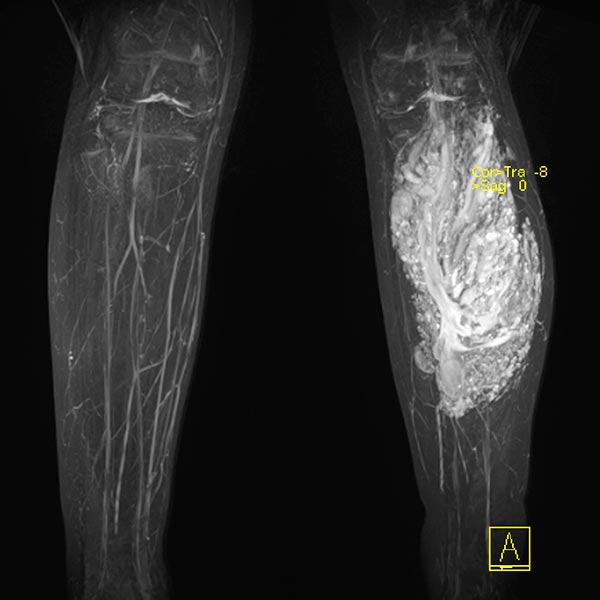

Die koronare T1-gewichtete native MRT zeigt eine intramuskuläre, gefäßreiche Läsion (isointens zur Muskulatur) mit deutlich zwischengelagertem hyperintensem Fettgewebe, mehr als bei einer normalen venösen Malformation üblich.

In der axialen T2-gewichteten MRT des linken Unterschenkels finden sich mehrere dilatierte, dysplastische Venen im Sinne einer venösen Malformation in der gesamten oberflächlichen Flexorenmuskulatur. Durch den niedrigen Durchfluss kommt es zur Stase des Blutes innerhalb der Malformation mit der Bildung von Flüssigkeits-Spiegeln. Praktisch der gesamte Muskel ist von Malformation und Fettgewebe durchsetzt. Großer Thrombus in einer dilatierten, dysplastischen Vene.

In der kontrastmittelunterstützen MR-Angiographie (MIP) zeigt sich ein komplettes Enhancement der venösen Malformationskomponente in der linken Wade mit Kontrastmittelpooling.